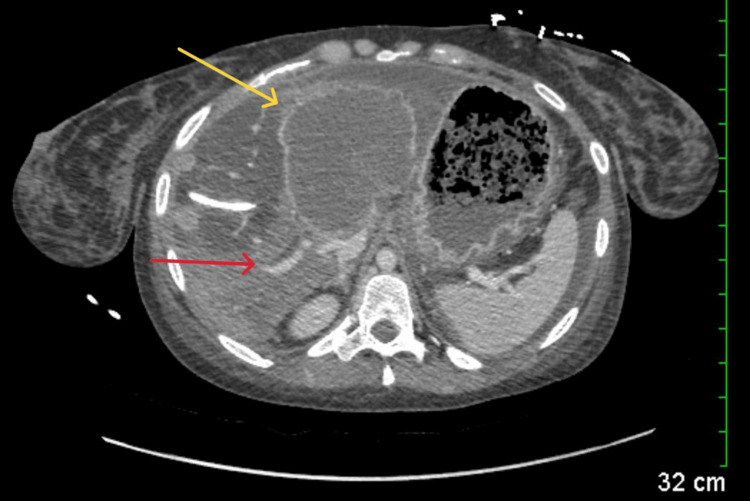

Abdominal computed tomography (CT) with IV contrast showed multiple peripherally enhancing masses within the liver, as well as bilateral intrahepatic biliary ductal dilation (Figure 1). Endoscopic ultrasound revealed multiple large solid masses in the liver consistent with metastases and excluded a fluid component, i.e., abscess. Due to the acute cholangitis, endoscopic retrograde cholangiopancreatography (ERCP) was performed, and the PTC drain was visualized emerging from the major papilla. The common bile duct was then cannulated using a balloon adjacent to the PTC drain, and contrast was injected. The cholangiogram showed a normal CBD and a mild stricture in the common hepatic duct, but the PTC drain was in an entirely separate ductal system (Figure 2A). A metal stent was then placed into the CBD and extended from the common hepatic duct to the major papilla (Figure 2B). The metal stent emerged from the major papilla adjacent to the PTC drain (Figure 3). Due to concern about the misplacement of the PTC drain, the interventional radiology (IR) team interrogated the drain using contrast (Figure 4). This revealed the presence of a DCBD, with the PTC drain placed in the right CBD and an endoscopically placed metal stent in the left CBD. Consecutive images from the contrast study showed a single proximal communication between the two CBDs. The IR team then removed the PTC drain, and a metal stent was placed in the right CBD, with both stents joining at the major papilla, thus confirming the presence of type Vb DCBD (Figure 5). Following the placement of both metal stents, the patient’s serum bilirubin levels normalized, and symptoms improved to where she was safely discharged home to continue her palliative chemotherapy regimen with her oncologist. Upon following up with her oncologist, her serum bilirubin was 1 mg/dL. The patient ultimately elected to pursue home hospice care shortly afterward.